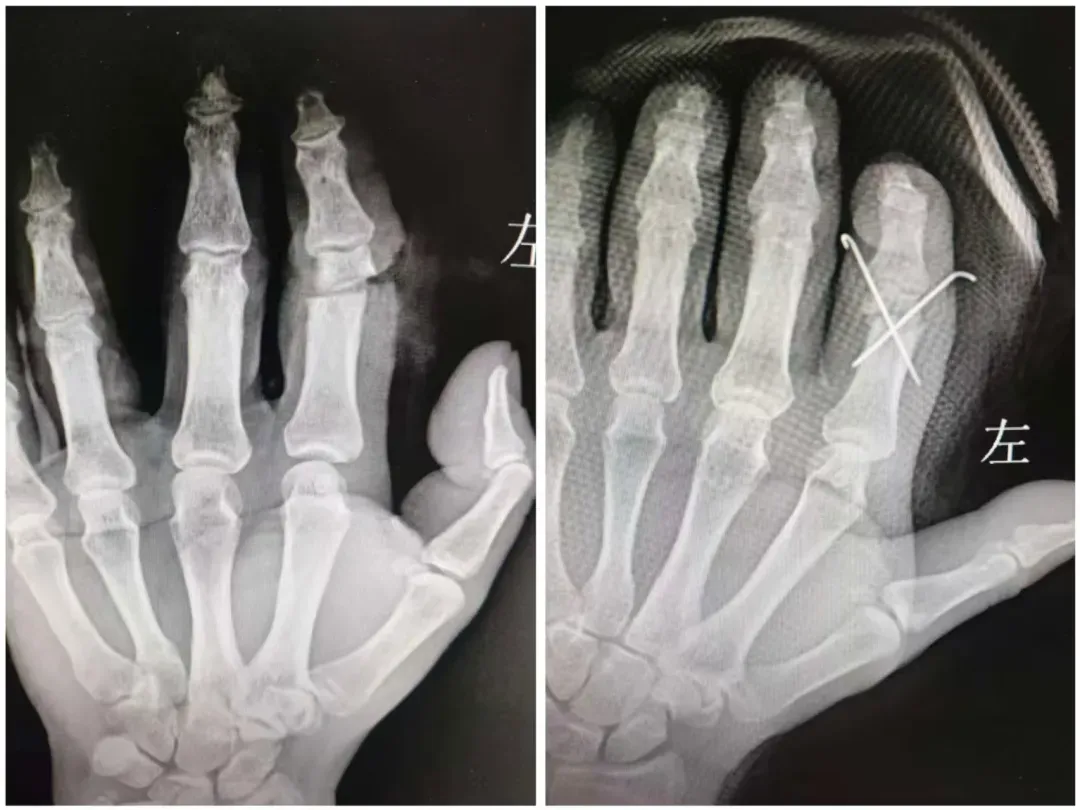

关节骨科(骨一科)团队争分夺秒完成了术前准备,手术正式开始!断指再植难度极高,手指血管直径仅0.3—0.5毫米,需在10—16倍手术显微镜下操作,团队不仅需要在短时间内完成清创、骨折复位固定、血管神经吻合、肌腱修复等多个复杂步骤,而且需要在极细的血管上“穿针引线”,这对于医生的显微操作技术有着极高要求。最终历时4小时,麻醉、清创、固定、吻合、缝皮,整场手术在精细操作下顺利完成。这场指尖上的“精雕细琢”终告功成——离断的食指由苍白转为温润红润,毛细血管充盈如初。

术前—术后